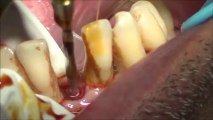

Dental Patient Education - Implant Placement

The Dental SideKick is InfoStars Dental Patient Education Program. To learn more about this amazing Dental Patient Education Program visit http://www.infostarproductions.com The Dental SideKick - Dental Patient Education - Dentistry Program